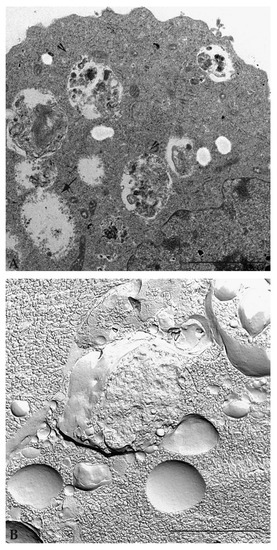

| Optical and electron microscopy | Display vacuoles inside the cytoplasm, their content, their stage of maturation, and the turnover of autophagic compartments |